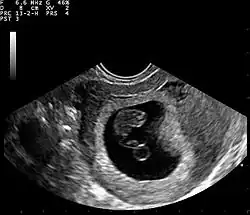

Gravidez intrauterina única, primeiro trimestre. O saco gestacional é visível (estrutura preta na ultrassonografia), contendo o polo fetal e o saco vitelino (estrutura circular abaixo do polo fetal).

A Ultrassonografia obstétrica também pode ser usada para detectar e diagnosticar a gravidez. É muito comum um teste de urina domiciliar positivo antes de uma ultrassonografia. Podem ser usadas tanto a abdominal quanto a vaginal, mas a vaginal permite uma visualização mais precoce da gestação. Com a ultrassonografia obstétrica, o saco gestacional (coleção intrauterina de líquido) pode ser visualizado entre 4,5 e 5 semanas de gestação, o saco vitelino entre 5 e 6 semanas e o polo fetal entre 5,5 e 6 semanas. O ultrassom é usado para diagnosticar gestação múltipla, o que não pode ser feito apenas pela presença de hCG na urina ou no sangue.[15] A determinação da idade gestacional do embrião/feto é outro benefício do ultrassom em comparação aos testes de hCG.[16]